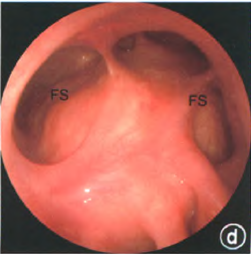

圖片顯示DraffIII型手術(shù)后寬大的額竇引流通道及清楚的暴露了前顱底